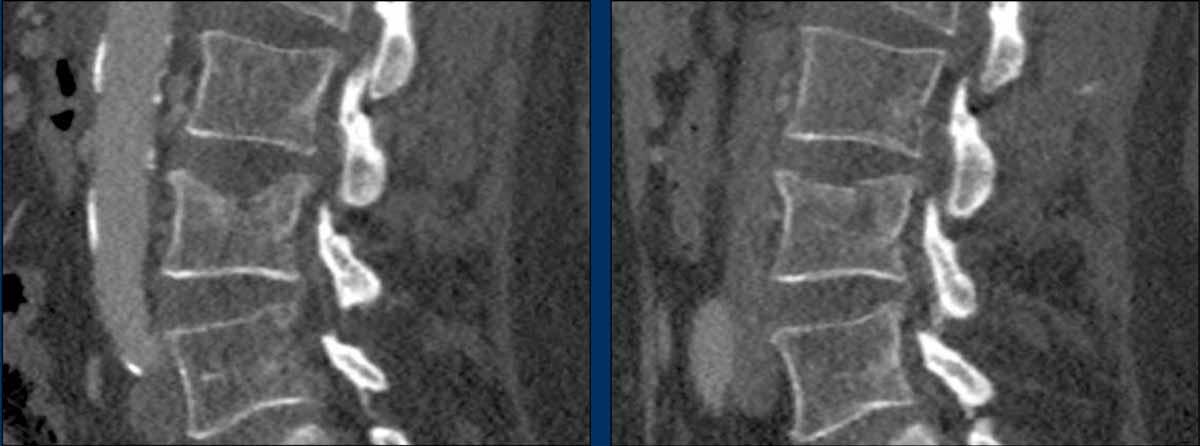

Here more examples of typical burst injuries.

Due to the axial force, the vertebral body is ‘split in half’, therefore a sagittal course of the fracture is common.

Therefore a fracture through the posterior osseous structures is possible in some type A injuries and should not always be regarded as a posterior distraction injury.

This can be confusing sometimes.

What is the highest AO-type of injury?

Findings

- No C or B injury.

- Fractures of the vertebral body with involvement of both endplates (1+1 points) and posterior wall (2 points).

- In the coronal plane, a sagittal course of the fracture is seen, which is common in burst fractures.

- Bulging of the posterior wall without any other signs of dislocation is the result of the burst fracture.

Therefore no C injury.

Conclusion

Injury type A4